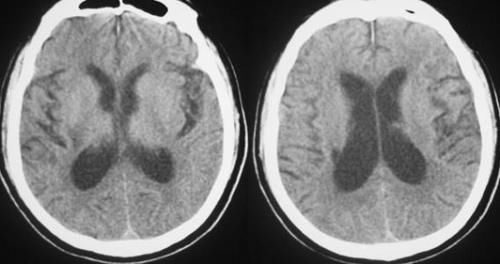

13岁孩子查出脑萎缩

雅慧之前学习成绩还不错,陈女士也经常会给他报一些补习班,然而上了六年级之后雅慧的成绩就一落千丈,常常闷闷不乐的,陈女士看孩子情绪低落也不忍心逼孩子,看孩子的试卷在很多默写的题上出错,想到可能使孩子的记忆力出现了问题,于是带孩子去医院做了个检查,没想到居然查出了脑萎缩,陈女士也惊呆了。想到自己平时工作忙,孩子一直跟爷爷奶奶住在一起,于是问了婆婆孩子平时的生活饮食情况,医生这才发现了问题所在。